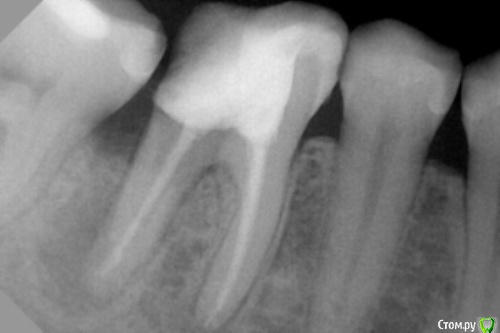

vse32 Опубликовано 30 ноября, 2016 Поделиться Опубликовано 30 ноября, 2016 Что Вы хотите закрывать МТА?Мне кажется, что трещина по бифуркации?В любом случае, на втором снимке после удаления штифта фатальная убыль тканей зуба в дистальной части. Протезирование, похоже там уже не вариант. Плюс киста.В общем, лечение титаном. Ссылка на комментарий

Kolchanov Опубликовано 30 ноября, 2016 Поделиться Опубликовано 30 ноября, 2016 (изменено) Из описания абсолютно не ясно где проблема. Видно только снижение плотности тканей зуба в области фуркации и дистального корня. Кстати, можно попробовать просто через окуляр микроскопа телефоном фотографировать. Мы когда учились, то на гистологии и патане удавалось препараты сфотографировать вполне сносно, а тогда телефончики были те еще. Изменено 30 ноября, 2016 пользователем Kolchanov Ссылка на комментарий

Kolchanov Опубликовано 30 ноября, 2016 Поделиться Опубликовано 30 ноября, 2016 Не знаю. Я тоже делал перфорации, но там как-то более экономные они выходили, закрывал. Фото бы помогло дать совет. На рентгенограмме выглядит подготовленным к удалению. Ссылка на комментарий

Паращук Роман Опубликовано 2 декабря, 2016 Поделиться Опубликовано 2 декабря, 2016 парадонтальная тонкаякупите насадки типа G8,G6,P3,E3. Удобно и анкера расшатывать и цемент в к/к убирать. Да и нависания дентина хорошо убирают. Если обходить анкер хороша ЕD4. У нее очень тонкий кончик,который еще можно заточить, уменьшив. Ну или у-файл,спредер с чаке.А так при неудобной форме и плохой визуализации,вы убили много дентина. Ссылка на комментарий